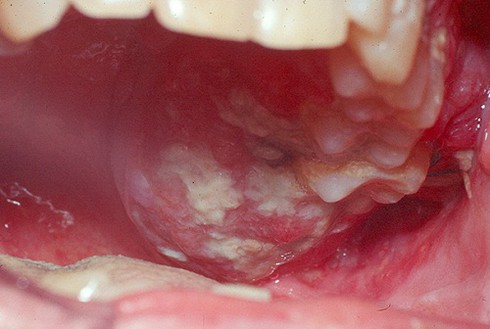

Ung thư khoang miệng |

Khoảng 2 tháng nay, vết lạ đó gây đau và bắt đầu loét. Bà Bền tới bệnh viện huyện khám được chẩn đoán viêm và được kê thuốc uống 15 ngày không có dấu hiệu đỡ. Bác sĩ khuyên bà nên tới cơ sở y tế lớn kiểm tra. Kết quả, tại bệnh viện bác sĩ chẩn đoán bà bị ung thư khoang miệng giai đoạn 2.

Các bác sĩ đã phát hiện khối u ở vùng má lên tới 3cm. Bà Bền được phẫu thuật cắt u và nạo vét hạch để triệt căn tế bào ung thư xung quanh. Cắt bỏ vùng má hàm và tái tạo lại khoang miệng.

Vết loét hoặc vết chồi lâu lành

Nếu như bạn nhận ấy những vết loét trên khoang miệng lâu lành trên một tháng, xuất hiện ở bất kỳ vị trí nào trong khoang miệng. Những vết loét này thường không đau, đụng nhẹ vào thấy hơi sượng cứng hoặc mất đi độ mềm mại. Đau thường xảy ra ở giai đoạn trễ hơn.